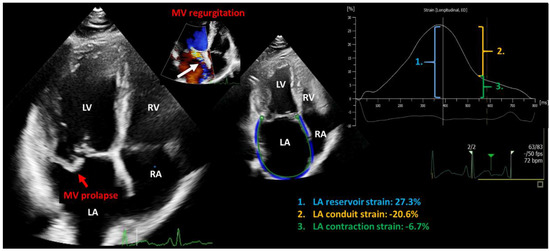

Figure 4.

Representative two-dimensional transthoracic echocardiography image showing primary mitral regurgitation due to prolapse of posterior mitral valve leaflet (red arrow) leading to eccentric mitral regurgitation (white arrow). The left atrial reservoir function is decreased (1.) LA: left atrium; RA: right atrium; LV: left ventricle; RV: right ventricle; MV: mitral valve; (2.) conduit strain; (3.) contraction strain.